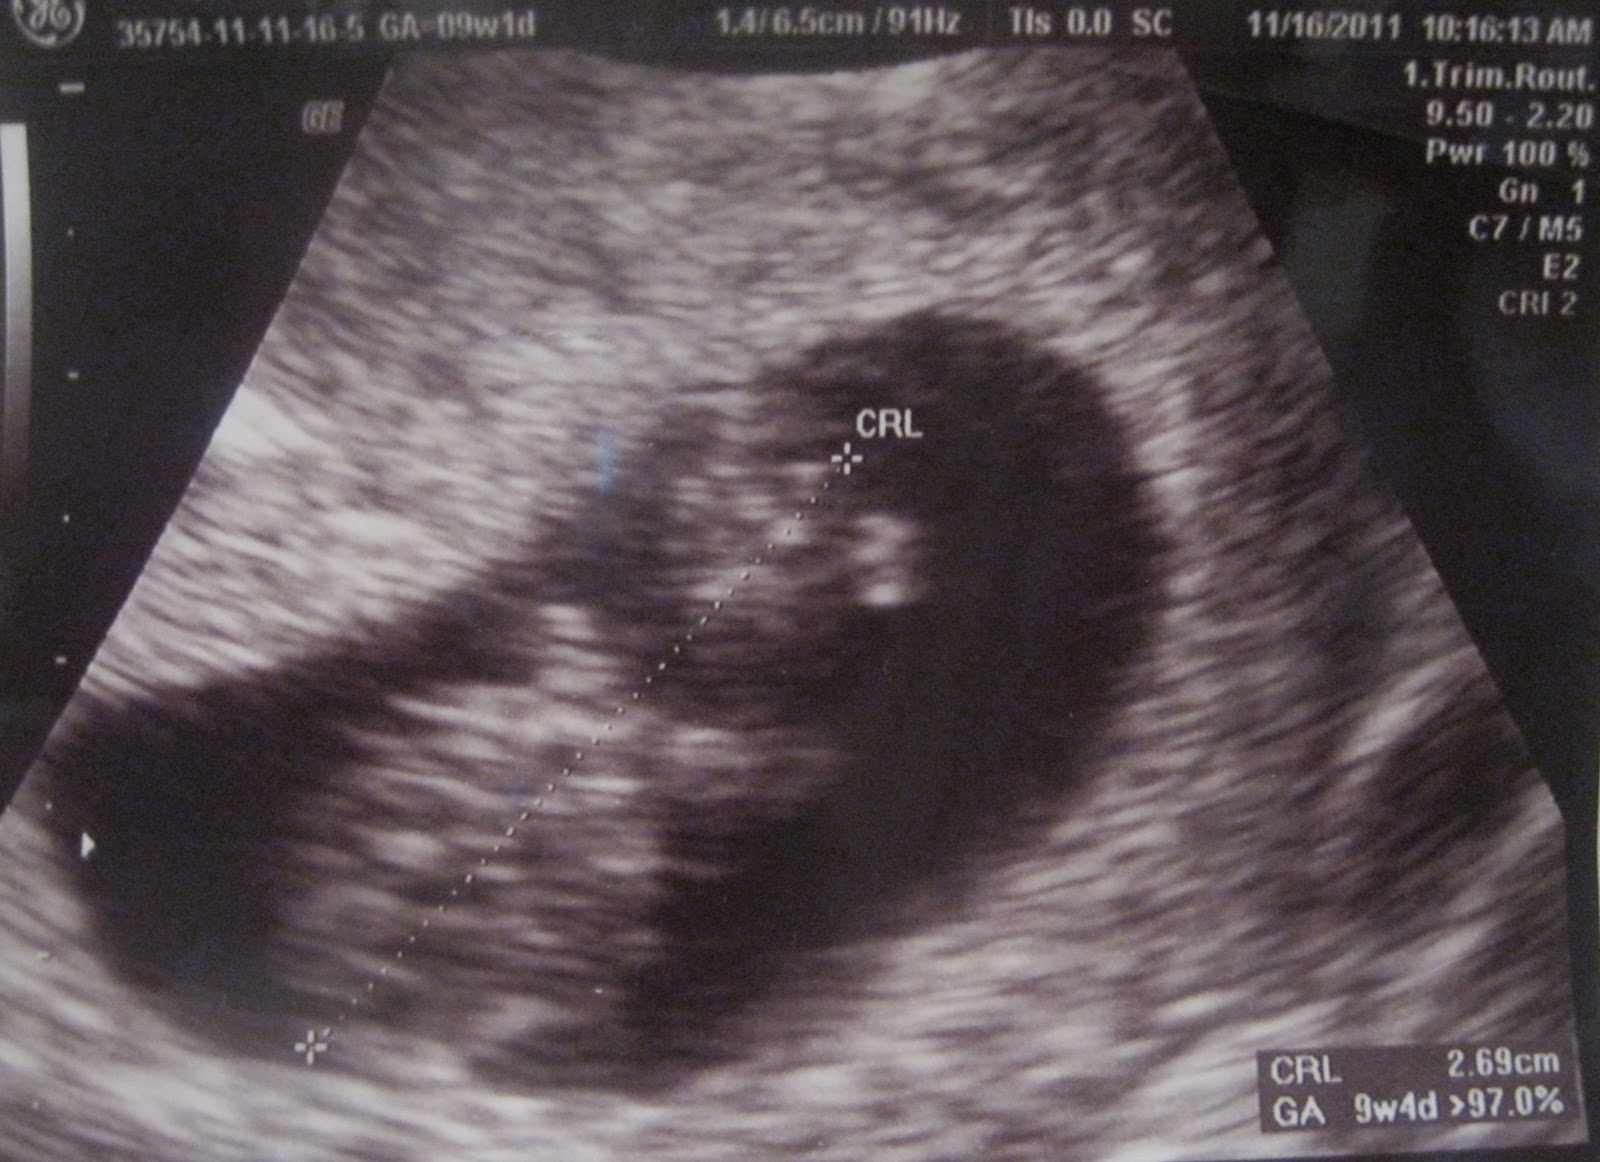

Not soon after that experience, we found out I was FINALLY pregnant. It was again one of the greatest moments of my life. I couldn't even believe that it was actually real...that I was pregnant!

Once we were more informed of my health issues, and were given the ok to try again, we assumed that it would again be a long time before I got pregnant. So its back to the same question: do we wait the "normal" amount of time between kids to start trying, and then have a long time before we even get pregnant? At that rate, I would be 90 before I had all 6-8 kids I think I want to have! I was also concerned that people would think I was wrong for having children closer together, or that Twodles would miss out on precious one on one time. We were also trying to time it right with school, health insurance, and all of that other stuff that makes paying for a baby an issue. I have no clue why it happened the way it did this time, but I got pregnant immediately!